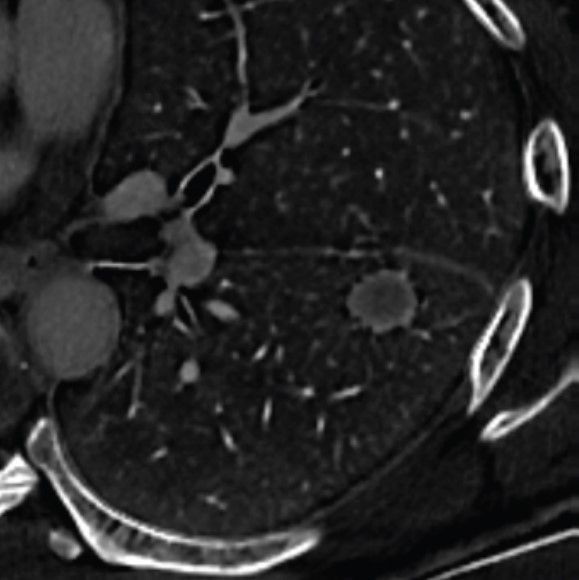

In the newly released Lung-RADS 2022 classification system for computed tomography (CT) lung cancer screening, the American College of Radiology (ACR) has noted a variety of updates including new classification criteria for atypical pulmonary cysts and airway nodules, time intervals for nodule growth and a new stepped management approach for Lung-RADS categories 3 and 4A.